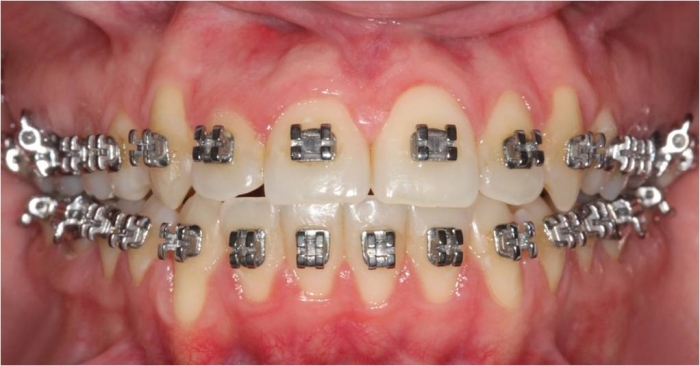

Mordida após a cirurgia